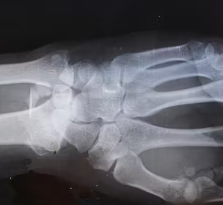

류마티스 관절염은 초기에는 증상이 서서히 나타나거나 다른 관절 질환으로 오인하기 쉽습니다. 손가락, 손목, 발가락 등 작은 관절에서 시작되는 경우가 많으며, 양쪽에 대칭적으로 나타나는 경향이 있습니다. 다음과 같은 증상들이 반복되거나 지속된다면 류마티스 관절염을 의심해 볼 수 있습니다.

관절이 붓고(부종), 열감이 느껴지며, 누르거나 움직일 때 통증이 나타납니다. 주로 손가락 중간 마디, 손목, 발가락 관절 등 여러 관절에 동시에 나타나고 양쪽에 대칭적으로 발생하는 경향이 있습니다.

통증은 휴식 시에도 나타날 수 있으며, 염증이 심할수록 통증과 부종이 심해집니다. 관절 주변 피부가 붉게 변하기도 합니다.